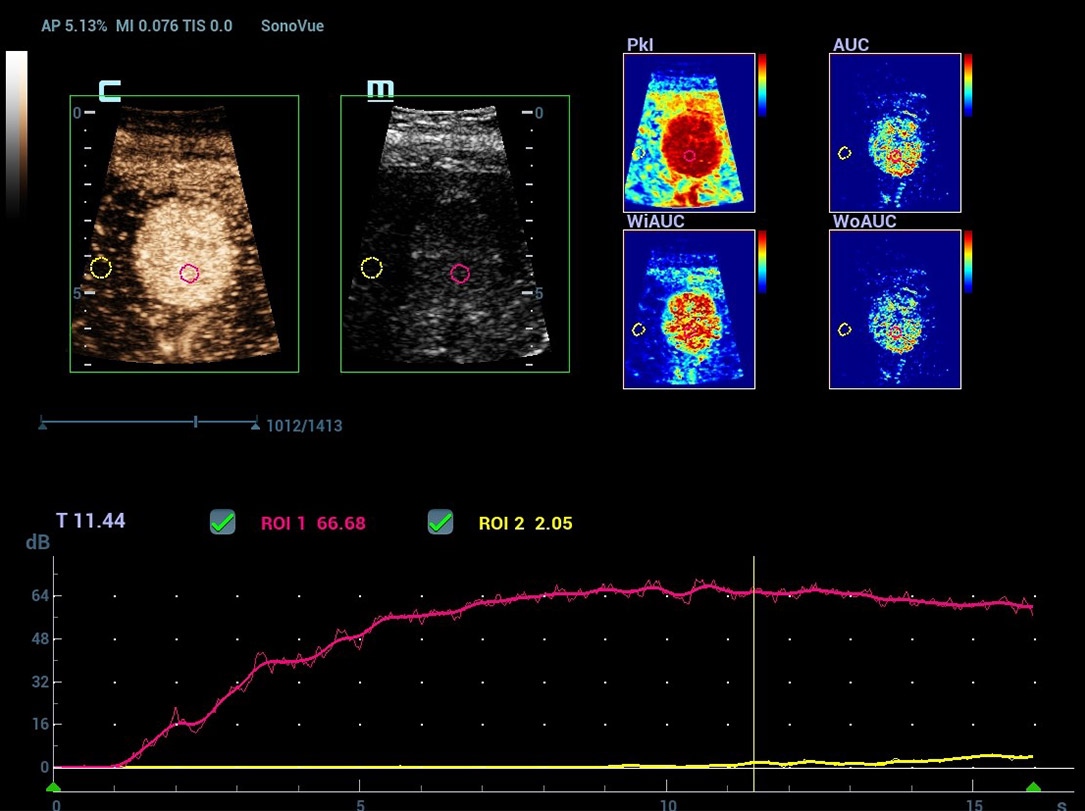

Nova CEUS QA (anûÀlise de quantifica??o)

Ferramentas de ponta para quantifica??o do CEUS

Nova anûÀlise de quantifica??o do CEUS

CEUS QA ã Tumor maligno de mama

A curva tempo-intensidade permite a anûÀlise quantitativa das imagens de CEUS. A nova QA CEUS fornece ferramentas de anûÀlise quantitativa de ponta para ajudar na avalia??o de tumores e na pesquisa clûÙnica.